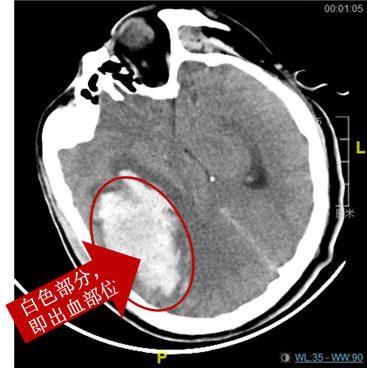

王先生今年42岁前天“突发左侧胳膊腿不能动”当地CT显示“脑出血”,转入昆山市一医院处于深度昏迷状态双眼瞳孔不等大右侧瞳孔直径5mm急诊诊断为“脑疝”。

脑出血形成的血肿占据了脑内正常组织的位置,在血肿周围的组织发生水肿,迫使正常脑组织受压,形成“脑疝”,王先生生命危急随时有心跳停止的可能,随时有生命危险。